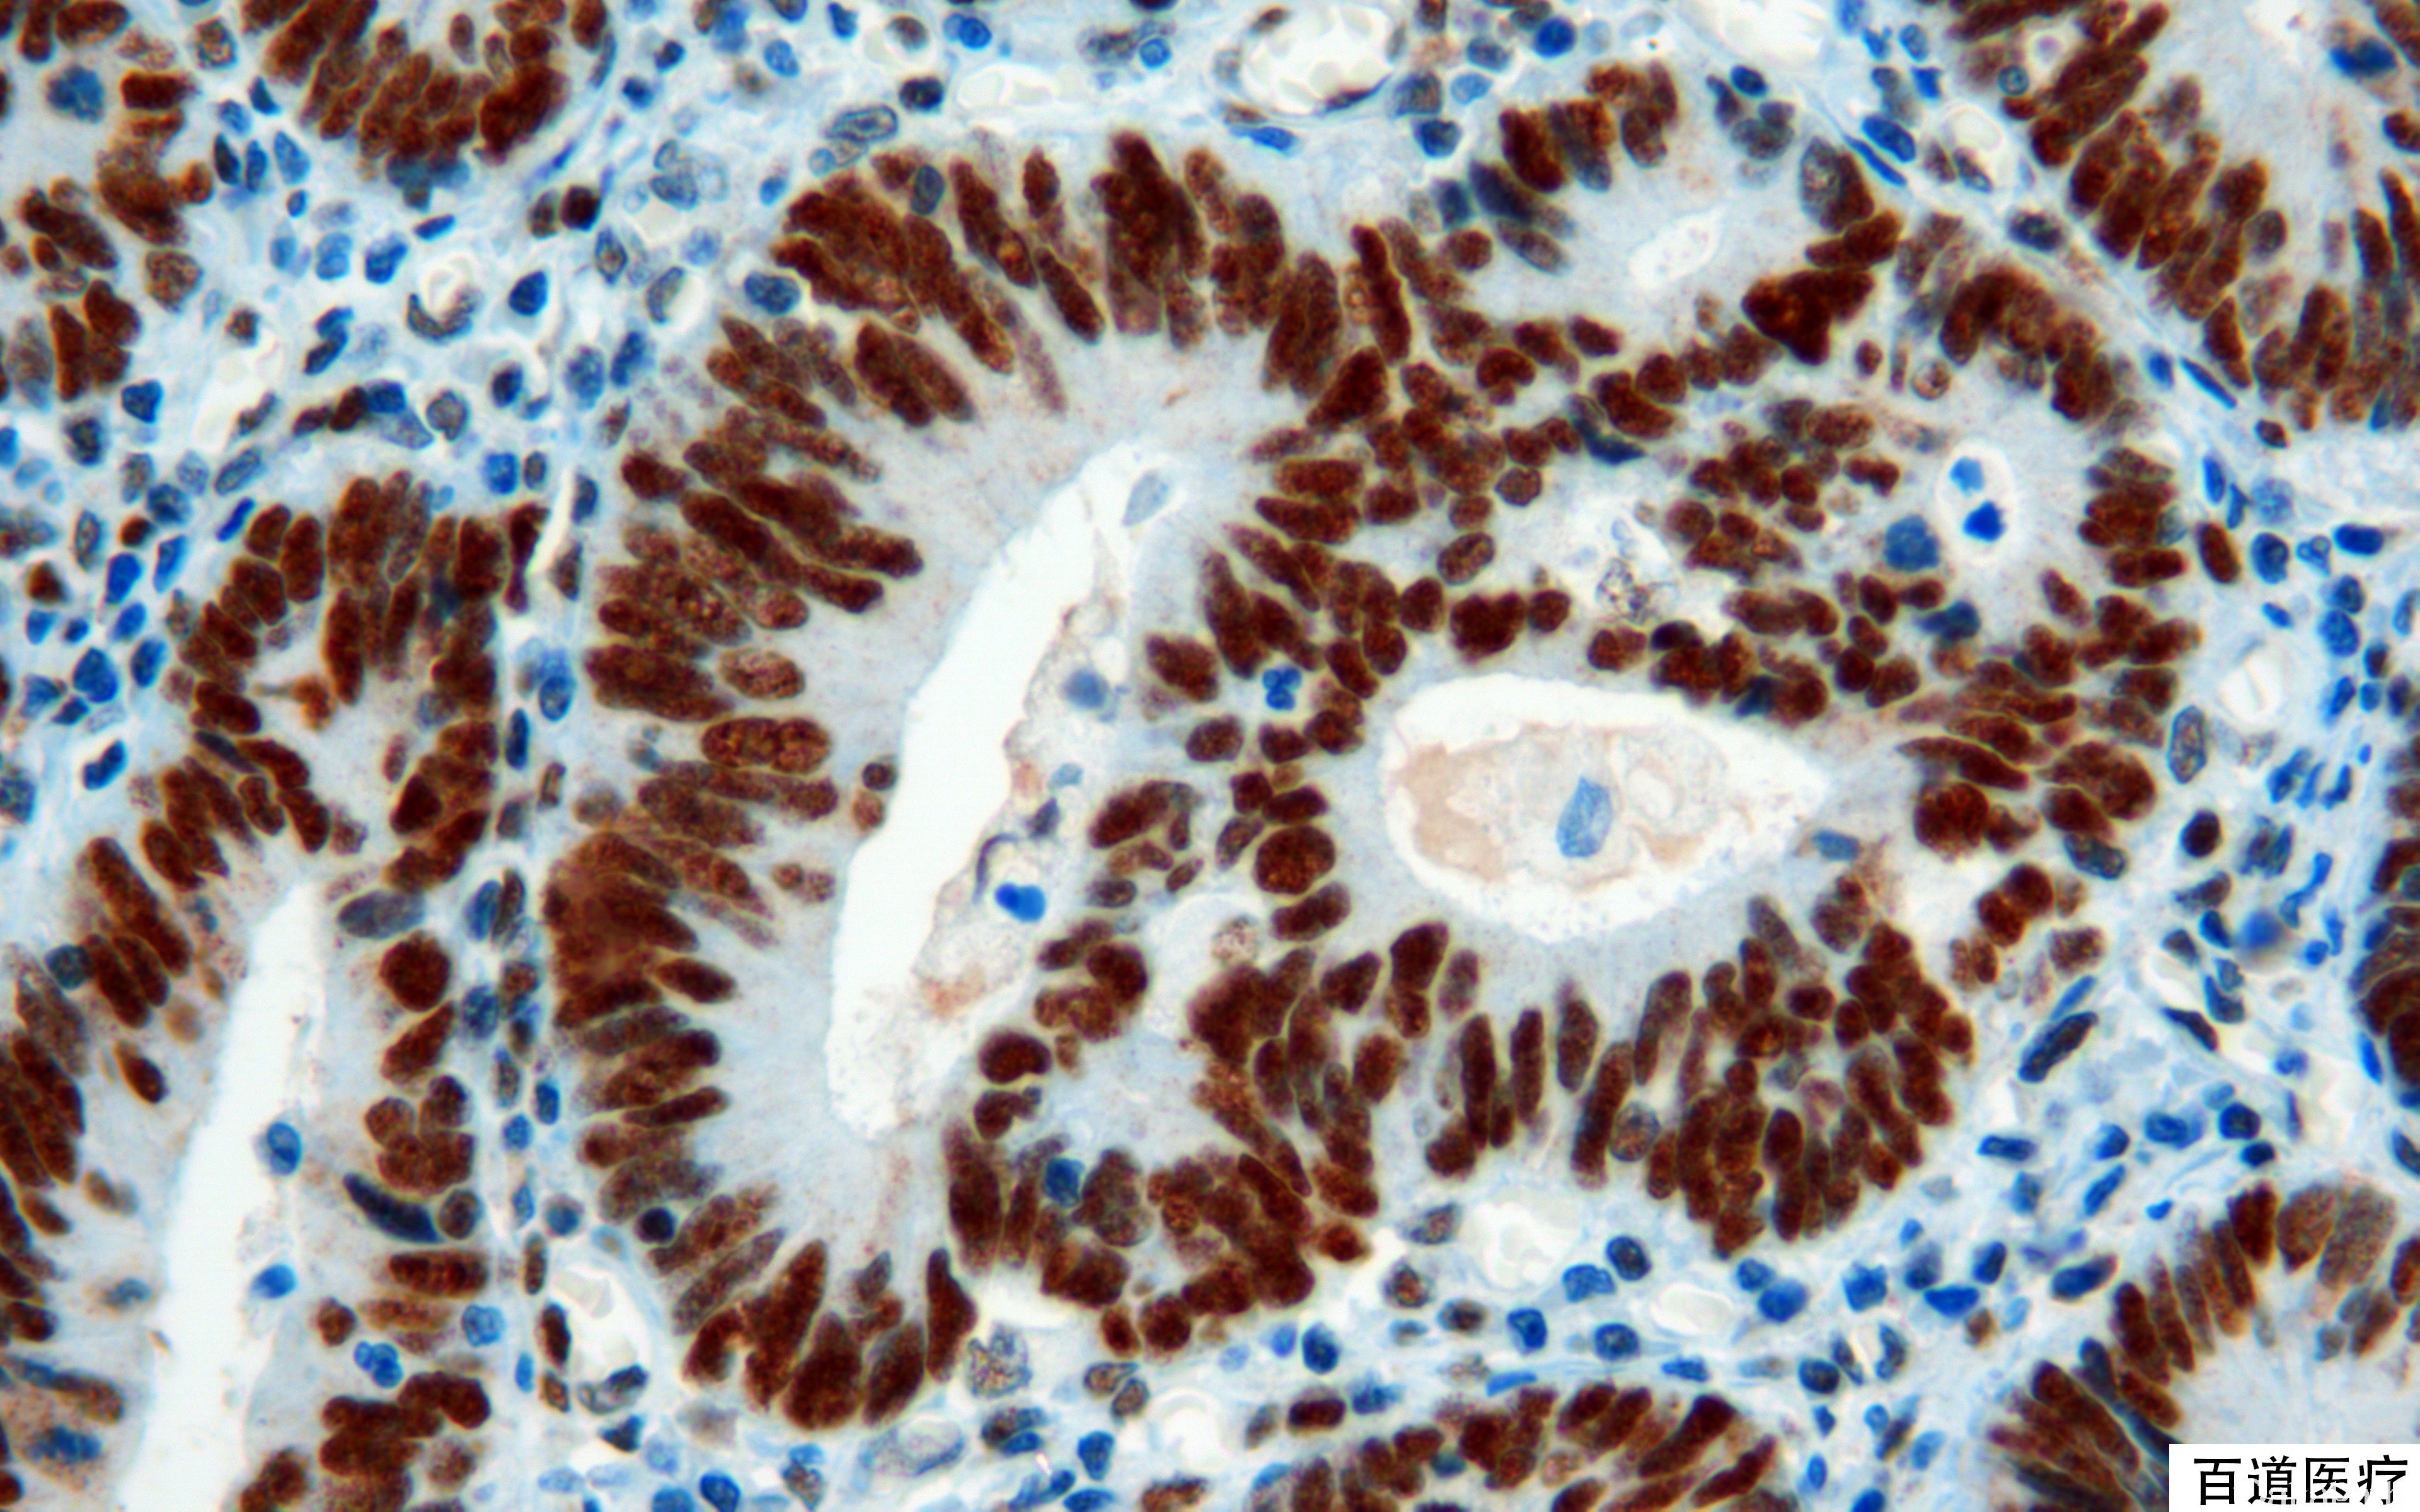

MSH2

与 MLH1 相似,为 DNA 错配修复基因,正常结肠黏膜细胞核阳性,突变后表达丢失。hMSH2 与 hMSH6 组成的复合体主要识别单个碱基的错配突变和短缺失或插入突变;hMSH3 组成的复合体主要识别长片段的插入或缺失突变。

信号定位: 胞核